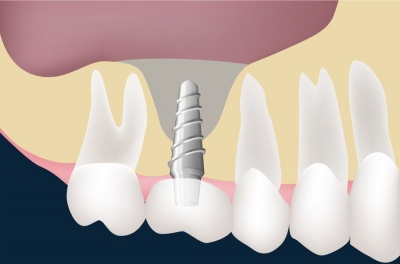

ПОКАЗАНИЯ К ПРИМЕНЕНИЮ.

Защита от потери частиц внесённого материала.

Закрытие различных перфораций.

Одномоментное использование при НТР (направленная тканевая регенерация).

Защита от нежелательного прорастания эпителия и попадания бактериальной флоры.

Поддержание объёма в местах восстановления костных дефектов.

СПОСОБ ПРИМЕНЕНИЯ.

При использовании мембран или флиса 3D «БИОМАТРИКС» необходимо соблюдать общие требования асептики, антисептики и лекарственной терапии.

После откидывания слизисто-надкостничного лоскута осуществляется доступ к костному дефекту.

Проводятся необходимые хирургические манипуляции.

Дефект заполняется остеопластическим материалом (например, ОСТЕОМАТРИКС, БИОИМПЛАНТ ГАП и т.д.) без лишней компрессии.

Вскрывается упаковка мембраны или флиса 3D.

Мембрана или флис 3D адаптируется по месту при помощи ножниц (возможно использование в качестве шаблона стерильной медицинской упаковочной бумаги). Основным требованием является перекрытие краёв дефекта на 2 мм и плотное соприкосновение с костью.

Мембрана или флис 3D укладывается поверх дефекта без дальнейшей обработки. Полная пенетрация мембраны или флиса 3D способствует лучшей адгезии и адаптации к костным структурам.

Следует избегать контакта со слюной и другими средами в целях минимизации контоминации бактериальными факторами.

Дополнительная фиксация мембраны или флиса 3D показана в случаях возможного смещения в результате излишнего давления на мягкие ткани в послеоперационном периоде.

Слизисто-надкостничный лоскут над мембраной или флисом 3D ушивается без натяжения.

Рана должна быть полностью закрыта во избежание ускоренного рассасывания и инфицирования.